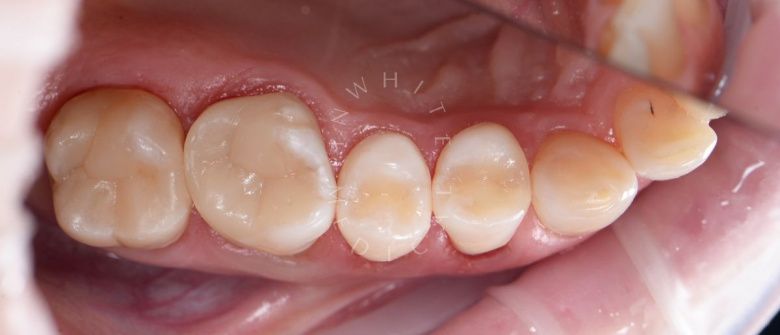

Лечение фиссурного кариеса под увеличением

Стоматология Москва лучшие клиники. Лечение фиссурного кариеса под увеличением - до процедуры

Стоматология Москва лучшие клиники. Лечение фиссурного кариеса под увеличением - после процедуры

До После